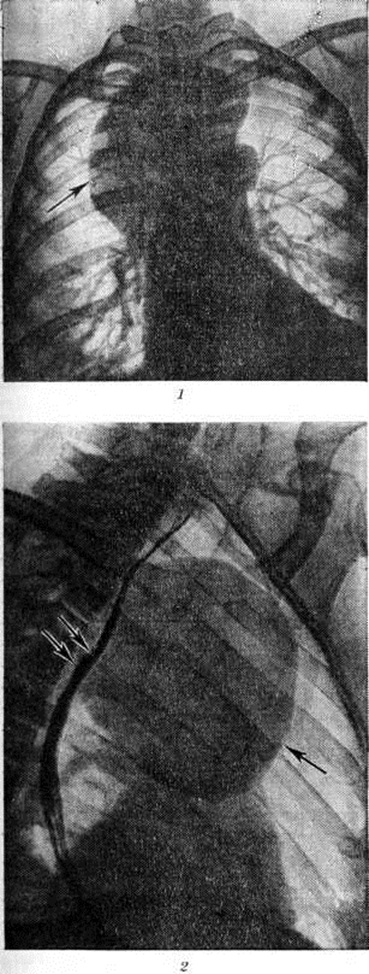

Рис. 1.

Микроскопическая картина стенки дермоидной кисты: 1—проток сальной железы; 2—многослойный плоский ороговевающий эпителий — внутренняя выстилка кисты; 3—сальные железы; × 24.

Дермоид обязательно содержит ткани, не характерные для данной области и не образующиеся в процессе метаплазии местных тканевых элементов. Дермоид обычно имеет округлую, не всегда правильную форму, гладкую или чуть бугристую поверхность. Величина его от долей сантиметра до крупных размеров. Консистенция плотноэластическая или тестоватая, неоднородная на различных участках. Дермоид бывает однокамерным и многокамерным, содержимое его — сало или желеобразные массы различной густоты, сероватого или буроватого цвета, с клубками волос. Комки сальной массы состоят из слущённых клеток плоского эпителия, кристаллов холестерина и аморфного жира; стенка кисты состоит из плотной соединительной ткани с участками обызвествления, иногда содержит хрящевую или костную ткань. Внутренняя поверхность часто имеет вид кожи и выстлана многослойным плоским эпителием (рисунок 1). Глубже расположены сальные и потовые железы, волосяные луковицы и обильная сосудистая сеть. Встречаются кисты, имеющие на внутренней поверхности возвышение — так называемый головной бугор. Он плотен, покрыт кожей и может содержать элементы всех трёх зародышевых листков. В некоторых Дермоид внутренняя поверхность на различном протяжении лишена эпителиальной выстилки, покрыта ржавого вида наложениями. Такой Дермоид называют абортивным или стареющим. Стенка его кое-где гиалинизирована, содержит лимфоцитарные инфильтраты, отложения гемосидерина, кристаллы холестерина, очаги ксантоматоза. Утрата эпителиальной выстилки, которая заменяется грануляционной тканью, значительно затрудняет диагностику. Дермоид возникает чаще в местах слияния и зарастания эмбриональных борозд и полостей, где образуются идущие вглубь складки эпидермиса. Встречается Дермоид в различных частях тела, но чаще всего в области головы, переднем средостении, и яичниках, в брюшной стенке, в толще забрюшинной и тазовой клетчатки, реже в печени, почках, головном мозге и его оболочках. При локализации на открытых частях тела Дермоид обнаруживаются в молодом возрасте. Дермоид, расположенные в клетчатке брюшной и тазовой области, в грудной полости, выявляются поздно, иногда сопровождаются болевыми ощущениями.